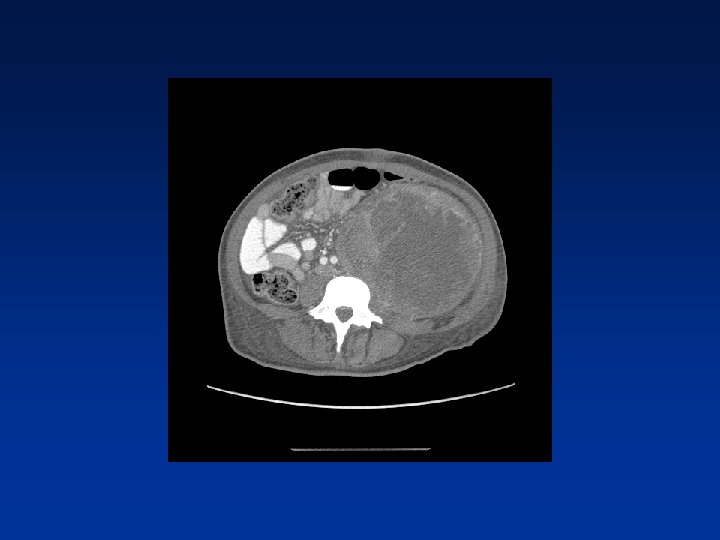

CASE